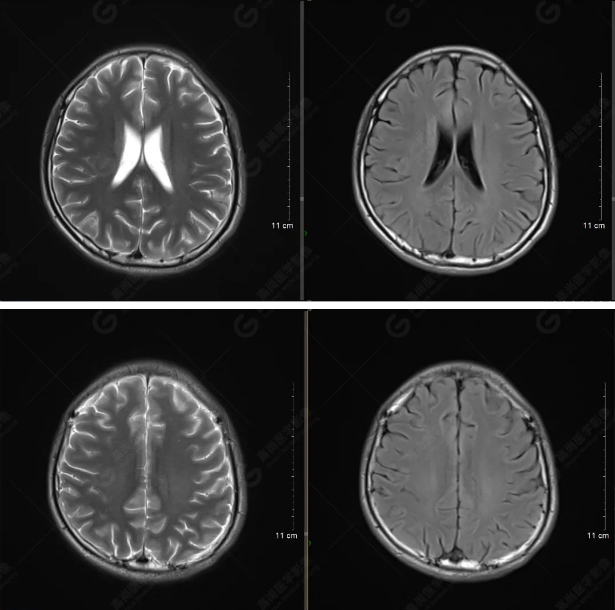

以下是平掃T2WI及FLAIR序列:

雙側(cè)大腦半球?qū)ΨQ,灰白質(zhì)對比正常,顱內(nèi)未見異常信號影。腦室系統(tǒng)未見擴(kuò)大,中線結(jié)構(gòu)居中。腦溝、裂未見增寬。幕下小腦、腦干未見異常。矢狀位示垂體形態(tài)、大小級信號未見異常。所示左側(cè)乳突內(nèi)見多發(fā)短T1長T2信號影。

顱腦MRI平掃未見明顯異常,左側(cè)乳突內(nèi)積血,建議補(bǔ)充SWI檢查。(左側(cè)為薄層原始圖像,右側(cè)為后處理5mm圖像)